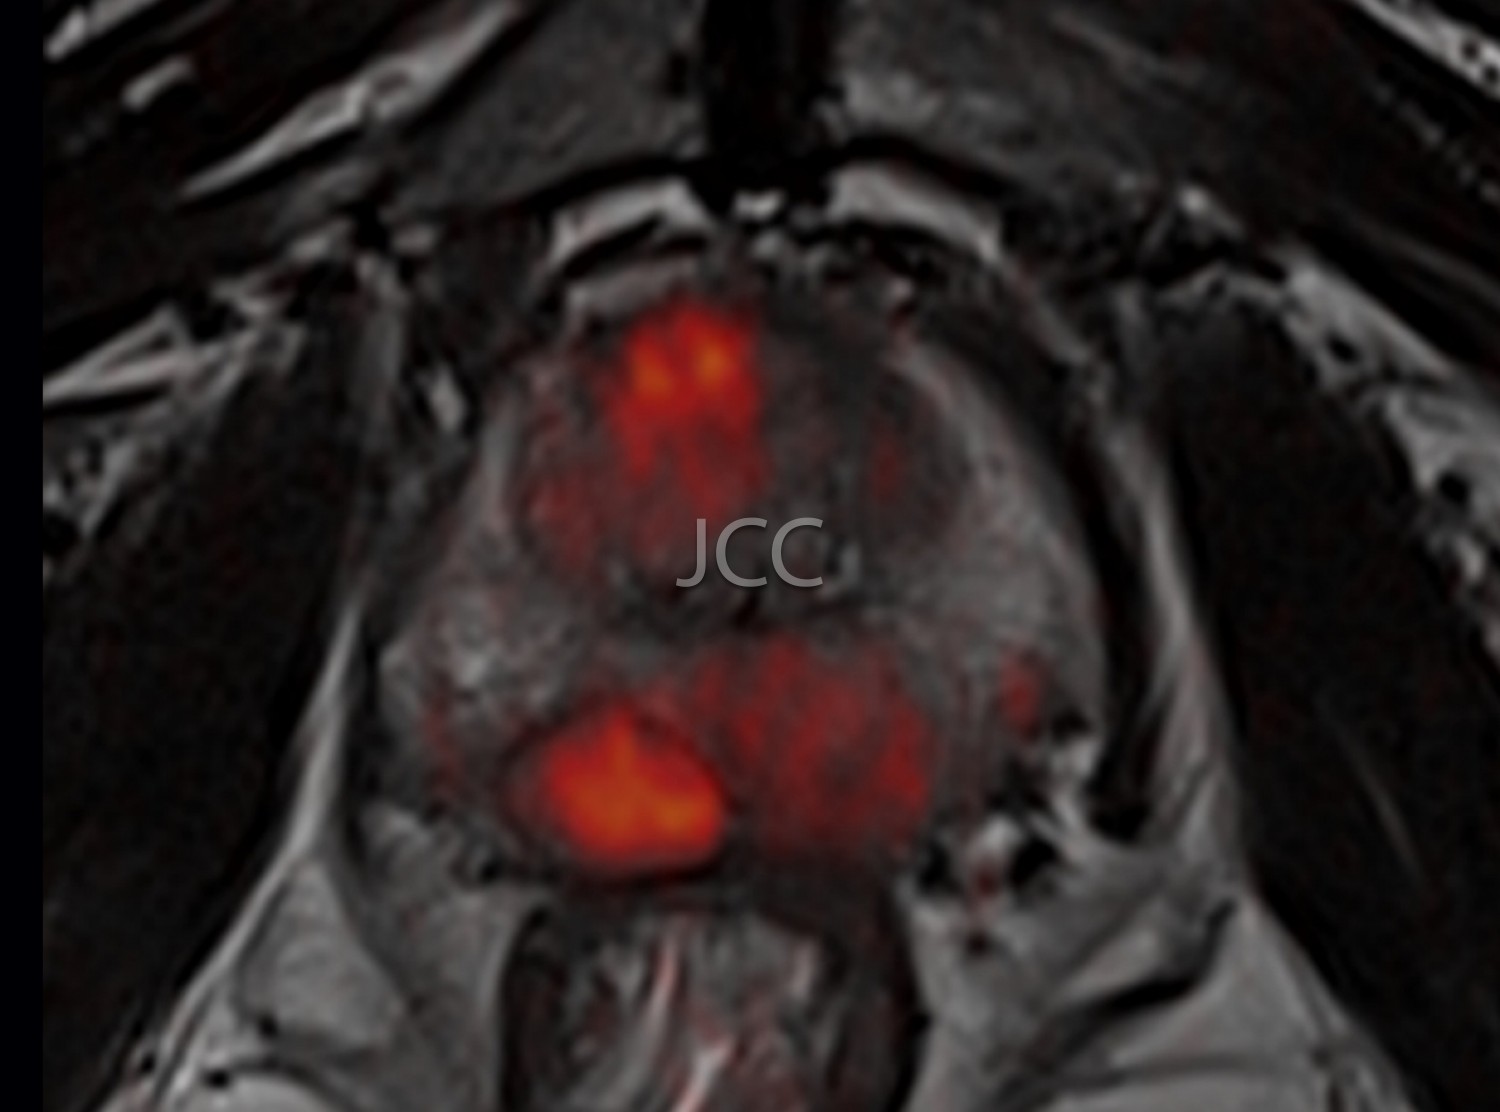

• RM da próstata

• RM Mamária